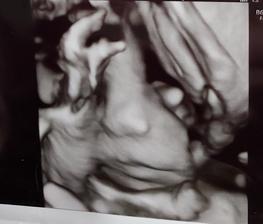

Druhé šťastie ❤

Zivot sa mi prevratil uplne o 180 stupnov.. viem vsak,ze nie som zdaleka ani prva ani posledna..

moj zivot- moje starosti/radosti..

Akoby tatino babatka povedal "NÁŠ ŽIVOT,NAŠE ŠTASTIE,NAŠA VOĽBA A NAŠA VEC"